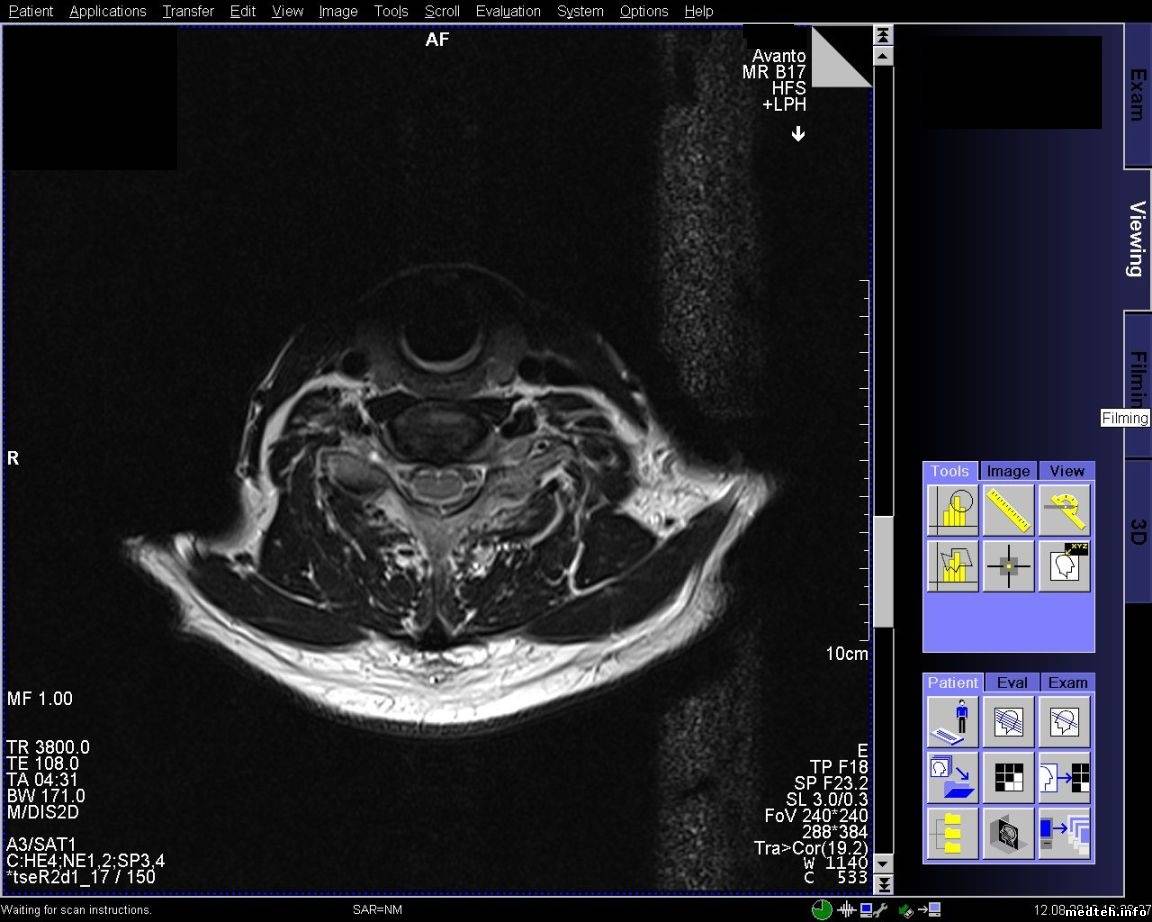

FedorM, спайк чек проходит, адвансед спайк чек не проходит. Выключал свет и инъектор, пробовал в разных комбинациях включать, адвансед спайк чек так и не проходит. Полосы появляются при обследовании с контрастом, но один раз было когда смотрели шею и коленку.

qa_1.pdf (135.4 Kb) · qa_2.pdf (126.1 Kb) · 5814388.jpg (197.7 Kb) · 8772789.jpg (220.4 Kb) · 6614537.jpg (206.3 Kb) · 3268821.jpg (226.4 Kb)

Всем доброго времени суток! Проблема с полосой так и остается актуальной. По снимку и протоколу было выяснено, что частота полосы ориентировочно 20-30 кГЦ, что соответствует частоте работы градиентов. Если гонять rf-noise, то помех (полос) не наблюдается. Полосы появляются на адвансед спайк чеке. Тест гоняли только на боди катушке и при этом если просто фантом лежит, то полоса может быть, а может и не быть. Но на паценте полоса стабильно стоит. Если положить на стол длинный провод и погонять адвансед спайк чек на боди катушке, то полоса стабильно проявляется. Следовательно пациент служит как бы антенной. Частота полосы в 20 кГц наводит на мысли, что неисправность в filter plate. Подскажите пожалуйста, что, где и как ещё можно посмотреть и проверить, если неисправность в filter plate, то как его проверить?